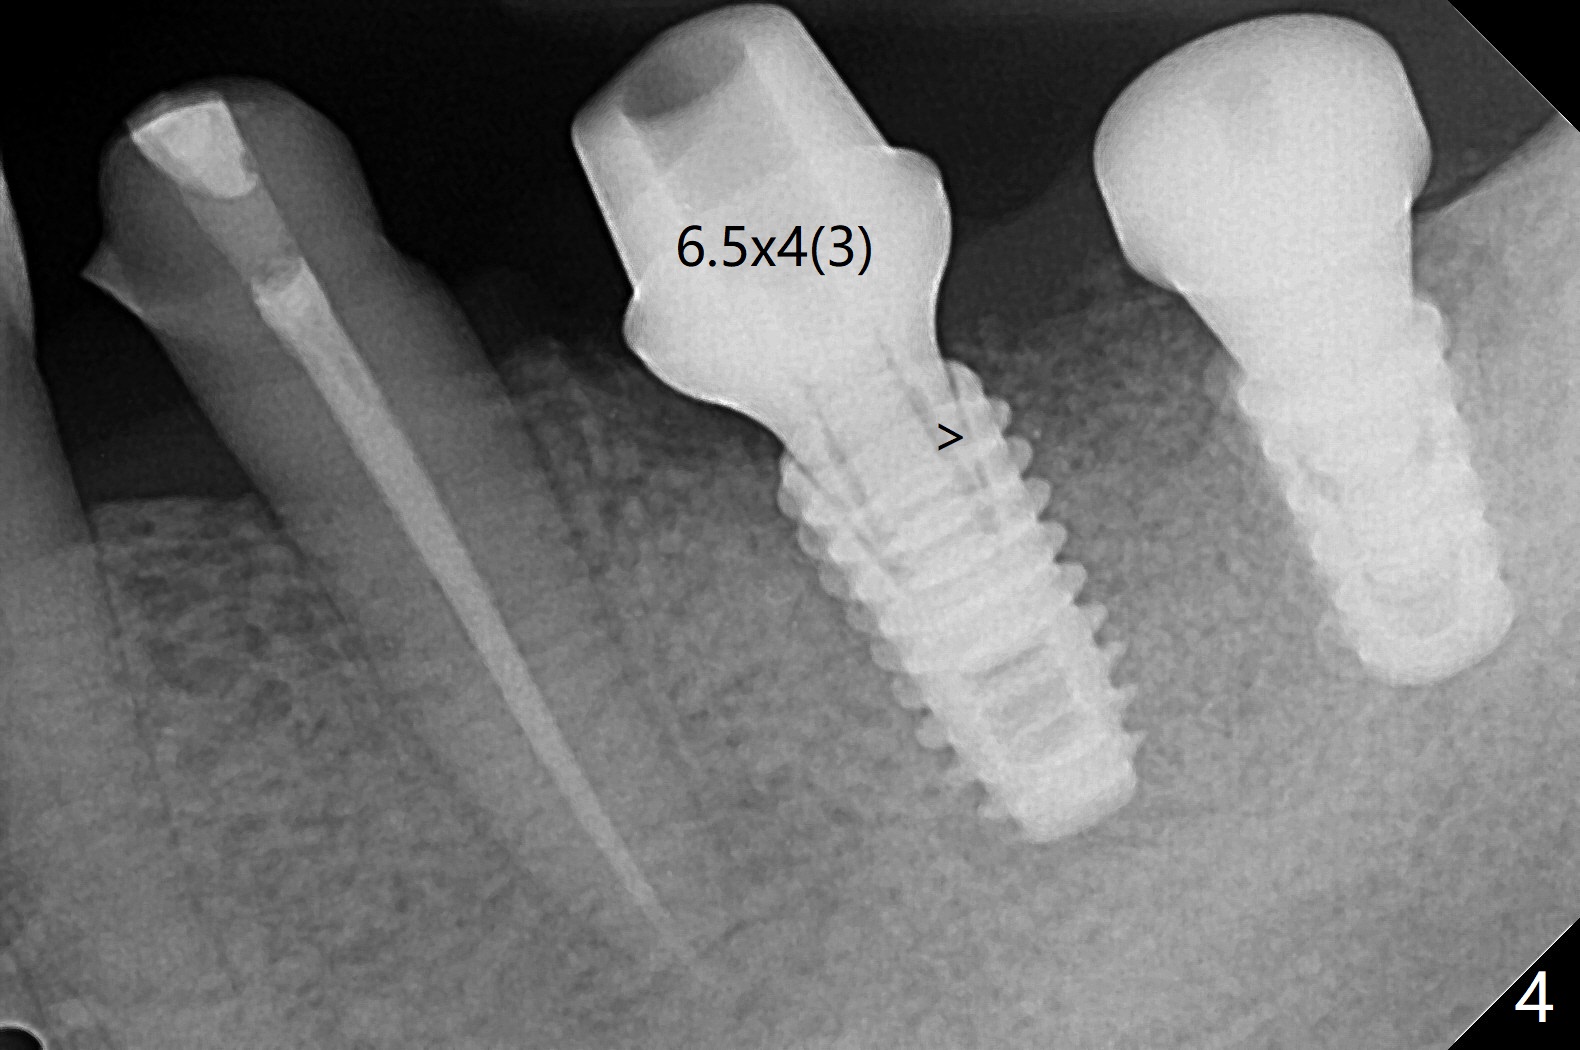

18,19导板远中架在17号牙残根表明树脂(图二:S),起到防止下沉作用,18号牙植体(~35Ncm)使用植体固定钉(fixture anchor mount no stop)植入,后者并且起着固定导板作用,增加19号牙植体植入稳定性,术中根尖片(图一)显示19号牙钻洞还不够深,之后钻头增加长度1.5毫米,4.5x8.5毫米植体扭力15-20Ncm(图二),但是与下齿槽神经管(红色虚线)还有很大距离,可能导板没有完全就位,植入后应该马上再次拍摄根尖片证实植入深度。由于18号牙区角化龈特别狭窄,切开种植,另外一个好处是容易植骨,但是术后疼痛明显,与上前牙即刻植牙(无切开)相比。今后尽量多做即刻种植。不过术后3个月包埋的植体表面有骨质覆盖(图三:*),二期手术很难找到愈合帽,而早些种植的上前牙植体由于过早受力,愈合不佳。当修复基台平面朝向颊侧,基台没有完全就位(图四:>)。当平面面对远中(图五:D),基台好像就位。